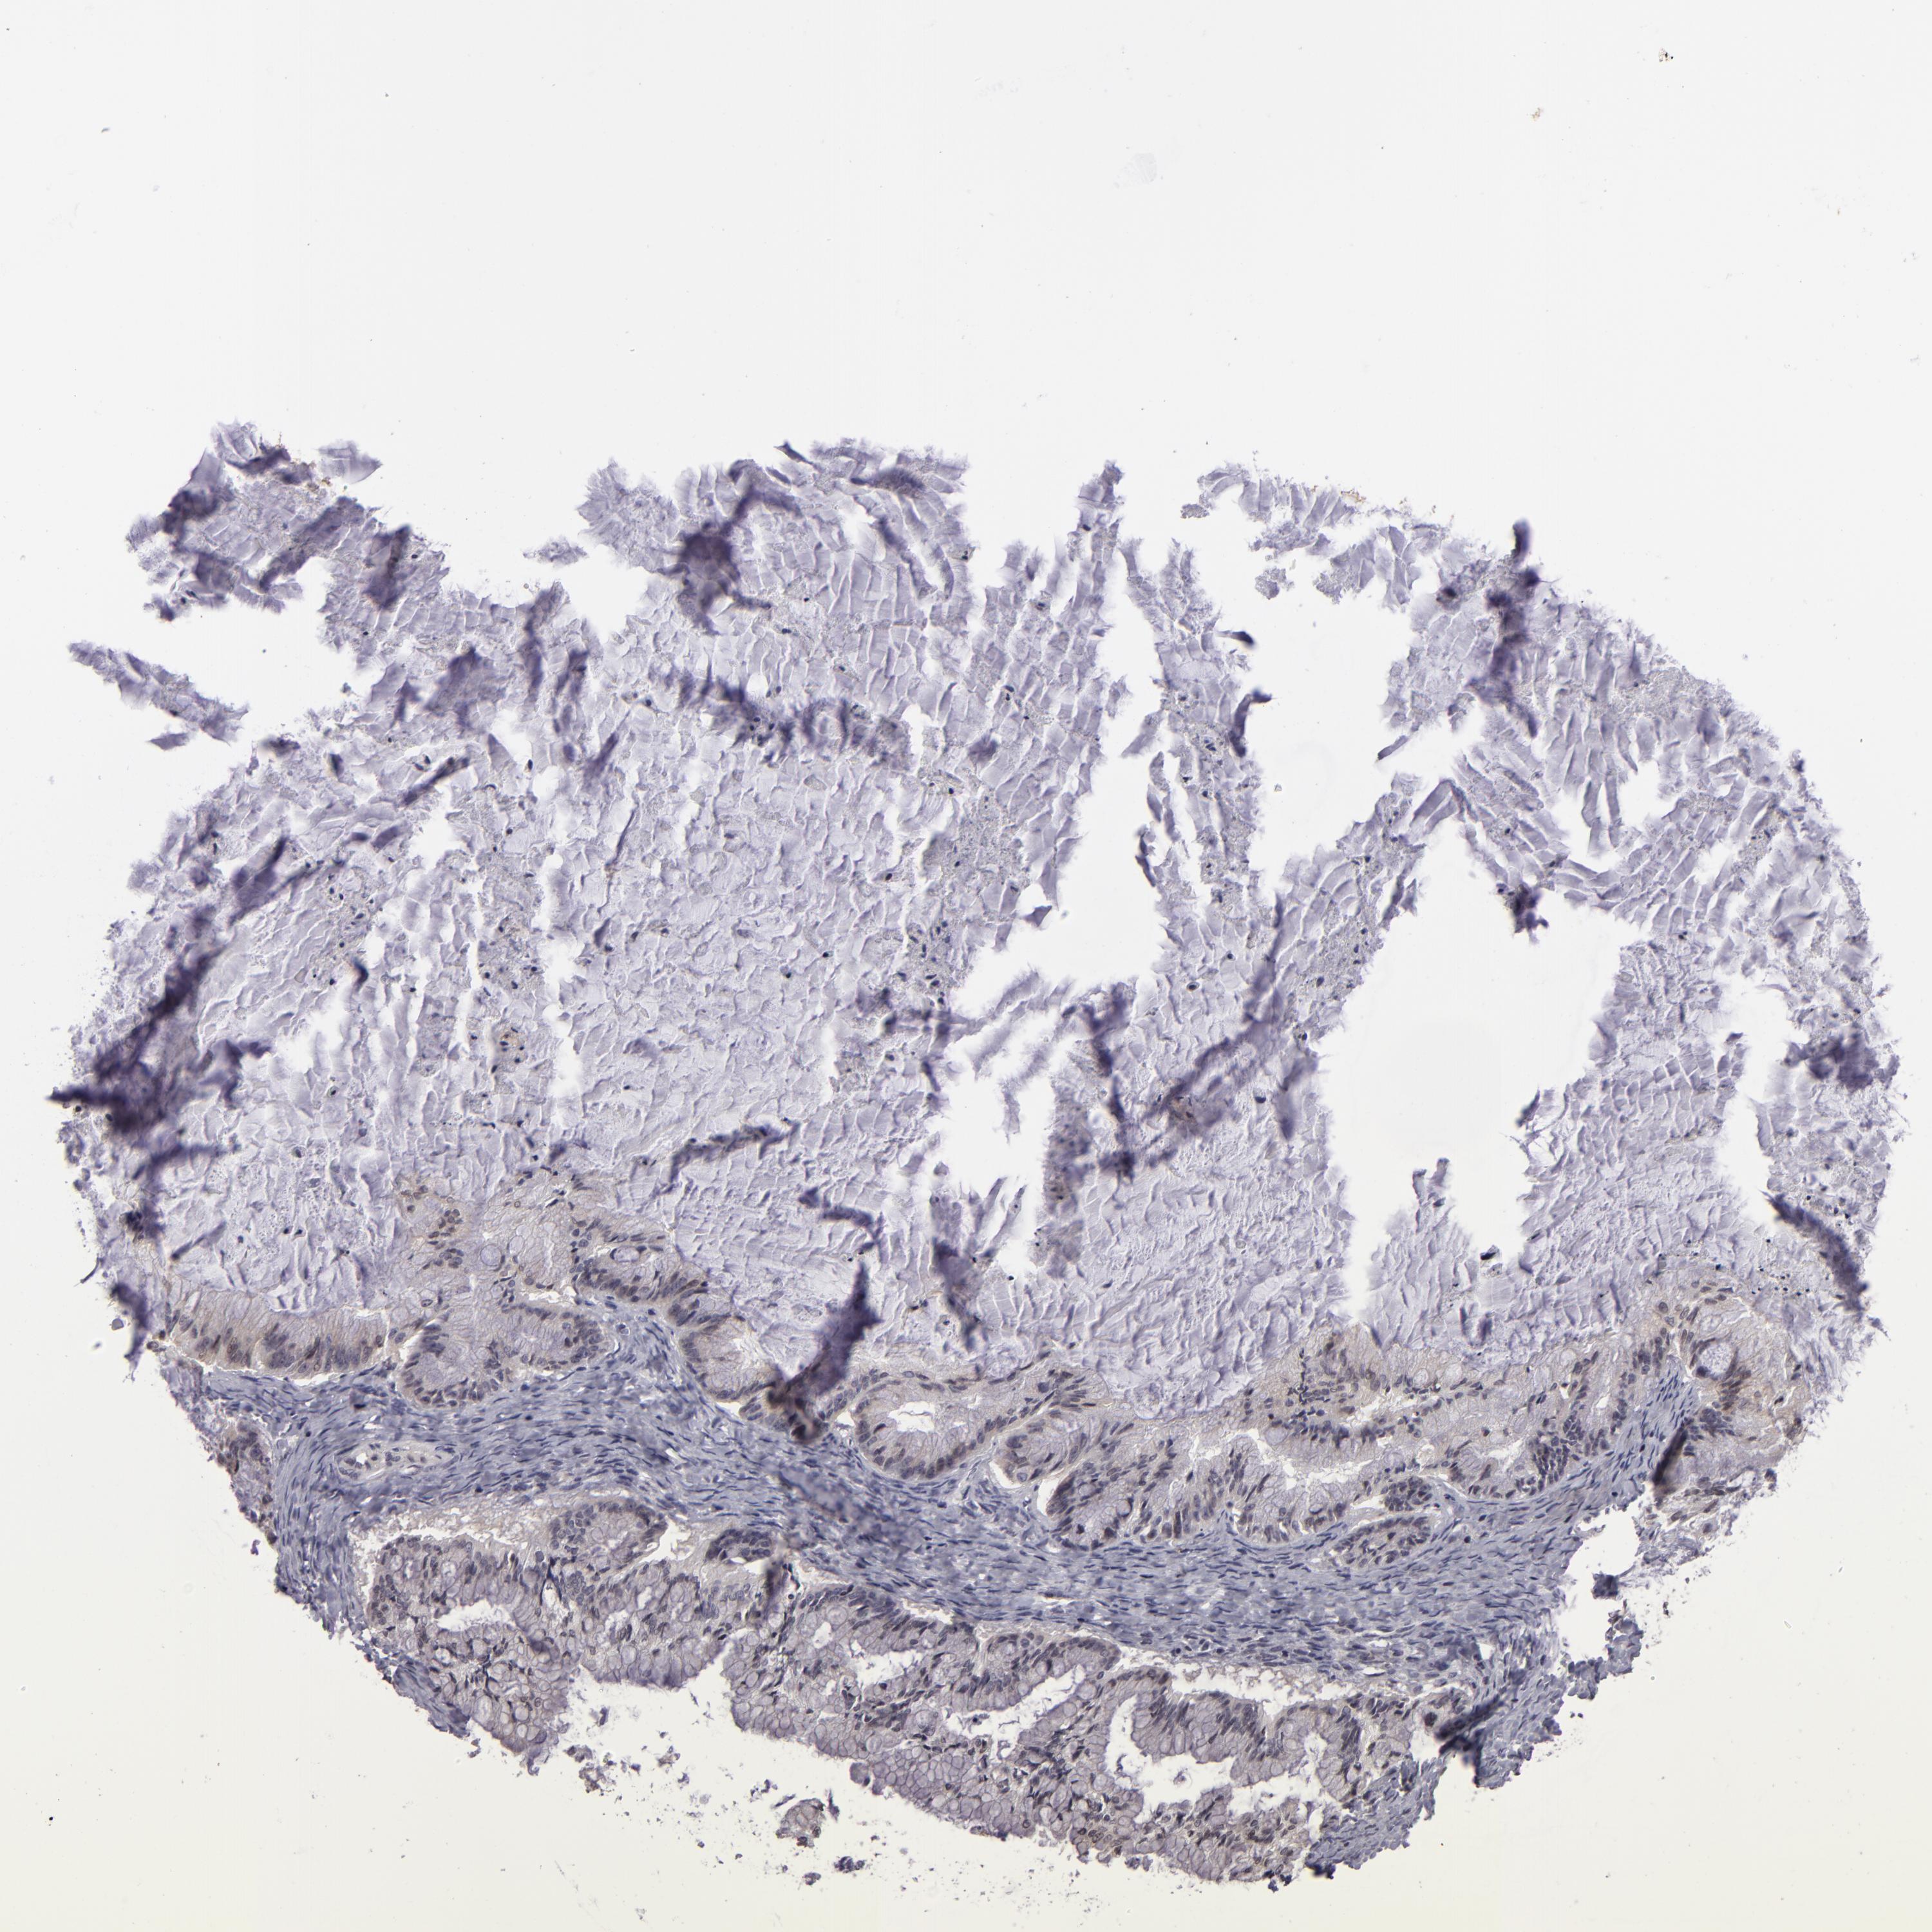

OVARIAN CANCER - Protein expressioni

A mouse-over function shows sample information and annotation data. Click on an image to view it in a full screen mode. Samples can be filtered based on level of antibody staining by selecting one or several of the following categories: high, medium, low and not detected. The assay and annotation is described here.

Note that samples used for immunohistochemistry by the Human Protein Atlas do not correspond to samples in the TCGA dataset.

Antibody stainingi

Antibody staining in the annotated cell types in the current human tissue is reported as not detected, low, medium, or high, based on conventional immunohistochemistry profiling in selected tissues. This score is based on the combination of the staining intensity and fraction of stained cells.

Each image is clickable and will lead to virtual microscopy that enables deeper exploration of all samples and also displays staining intensity scores, fraction scores and subcellular localization as well as patient and tissue information for each sample.

Antibody HPA048741

Antibody CAB001983

Cystadenocarcinoma, serous, NOS

Carcinoma, NOS

Cystadenocarcinoma, mucinous, NOS

Carcinoma, endometroid